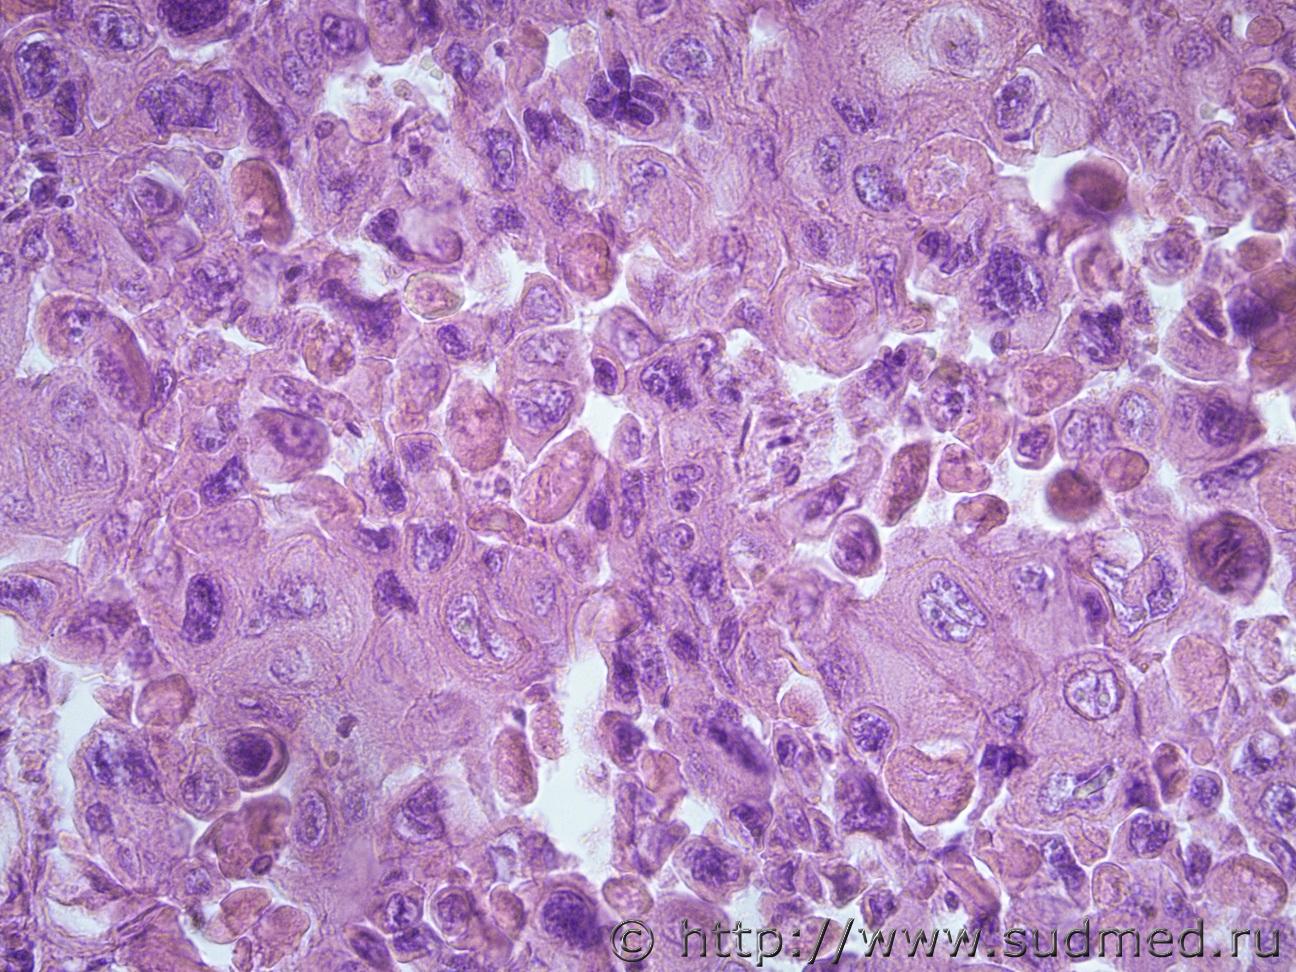

Опухоль стенки прямой кишки |

IVANNES Опухоль стенки прямой кишки 15.01.2019 - 13:58

Anton Что-то недифференцированное. 15.01.2019 - 14:45

griga Недифференцированная карцинома.